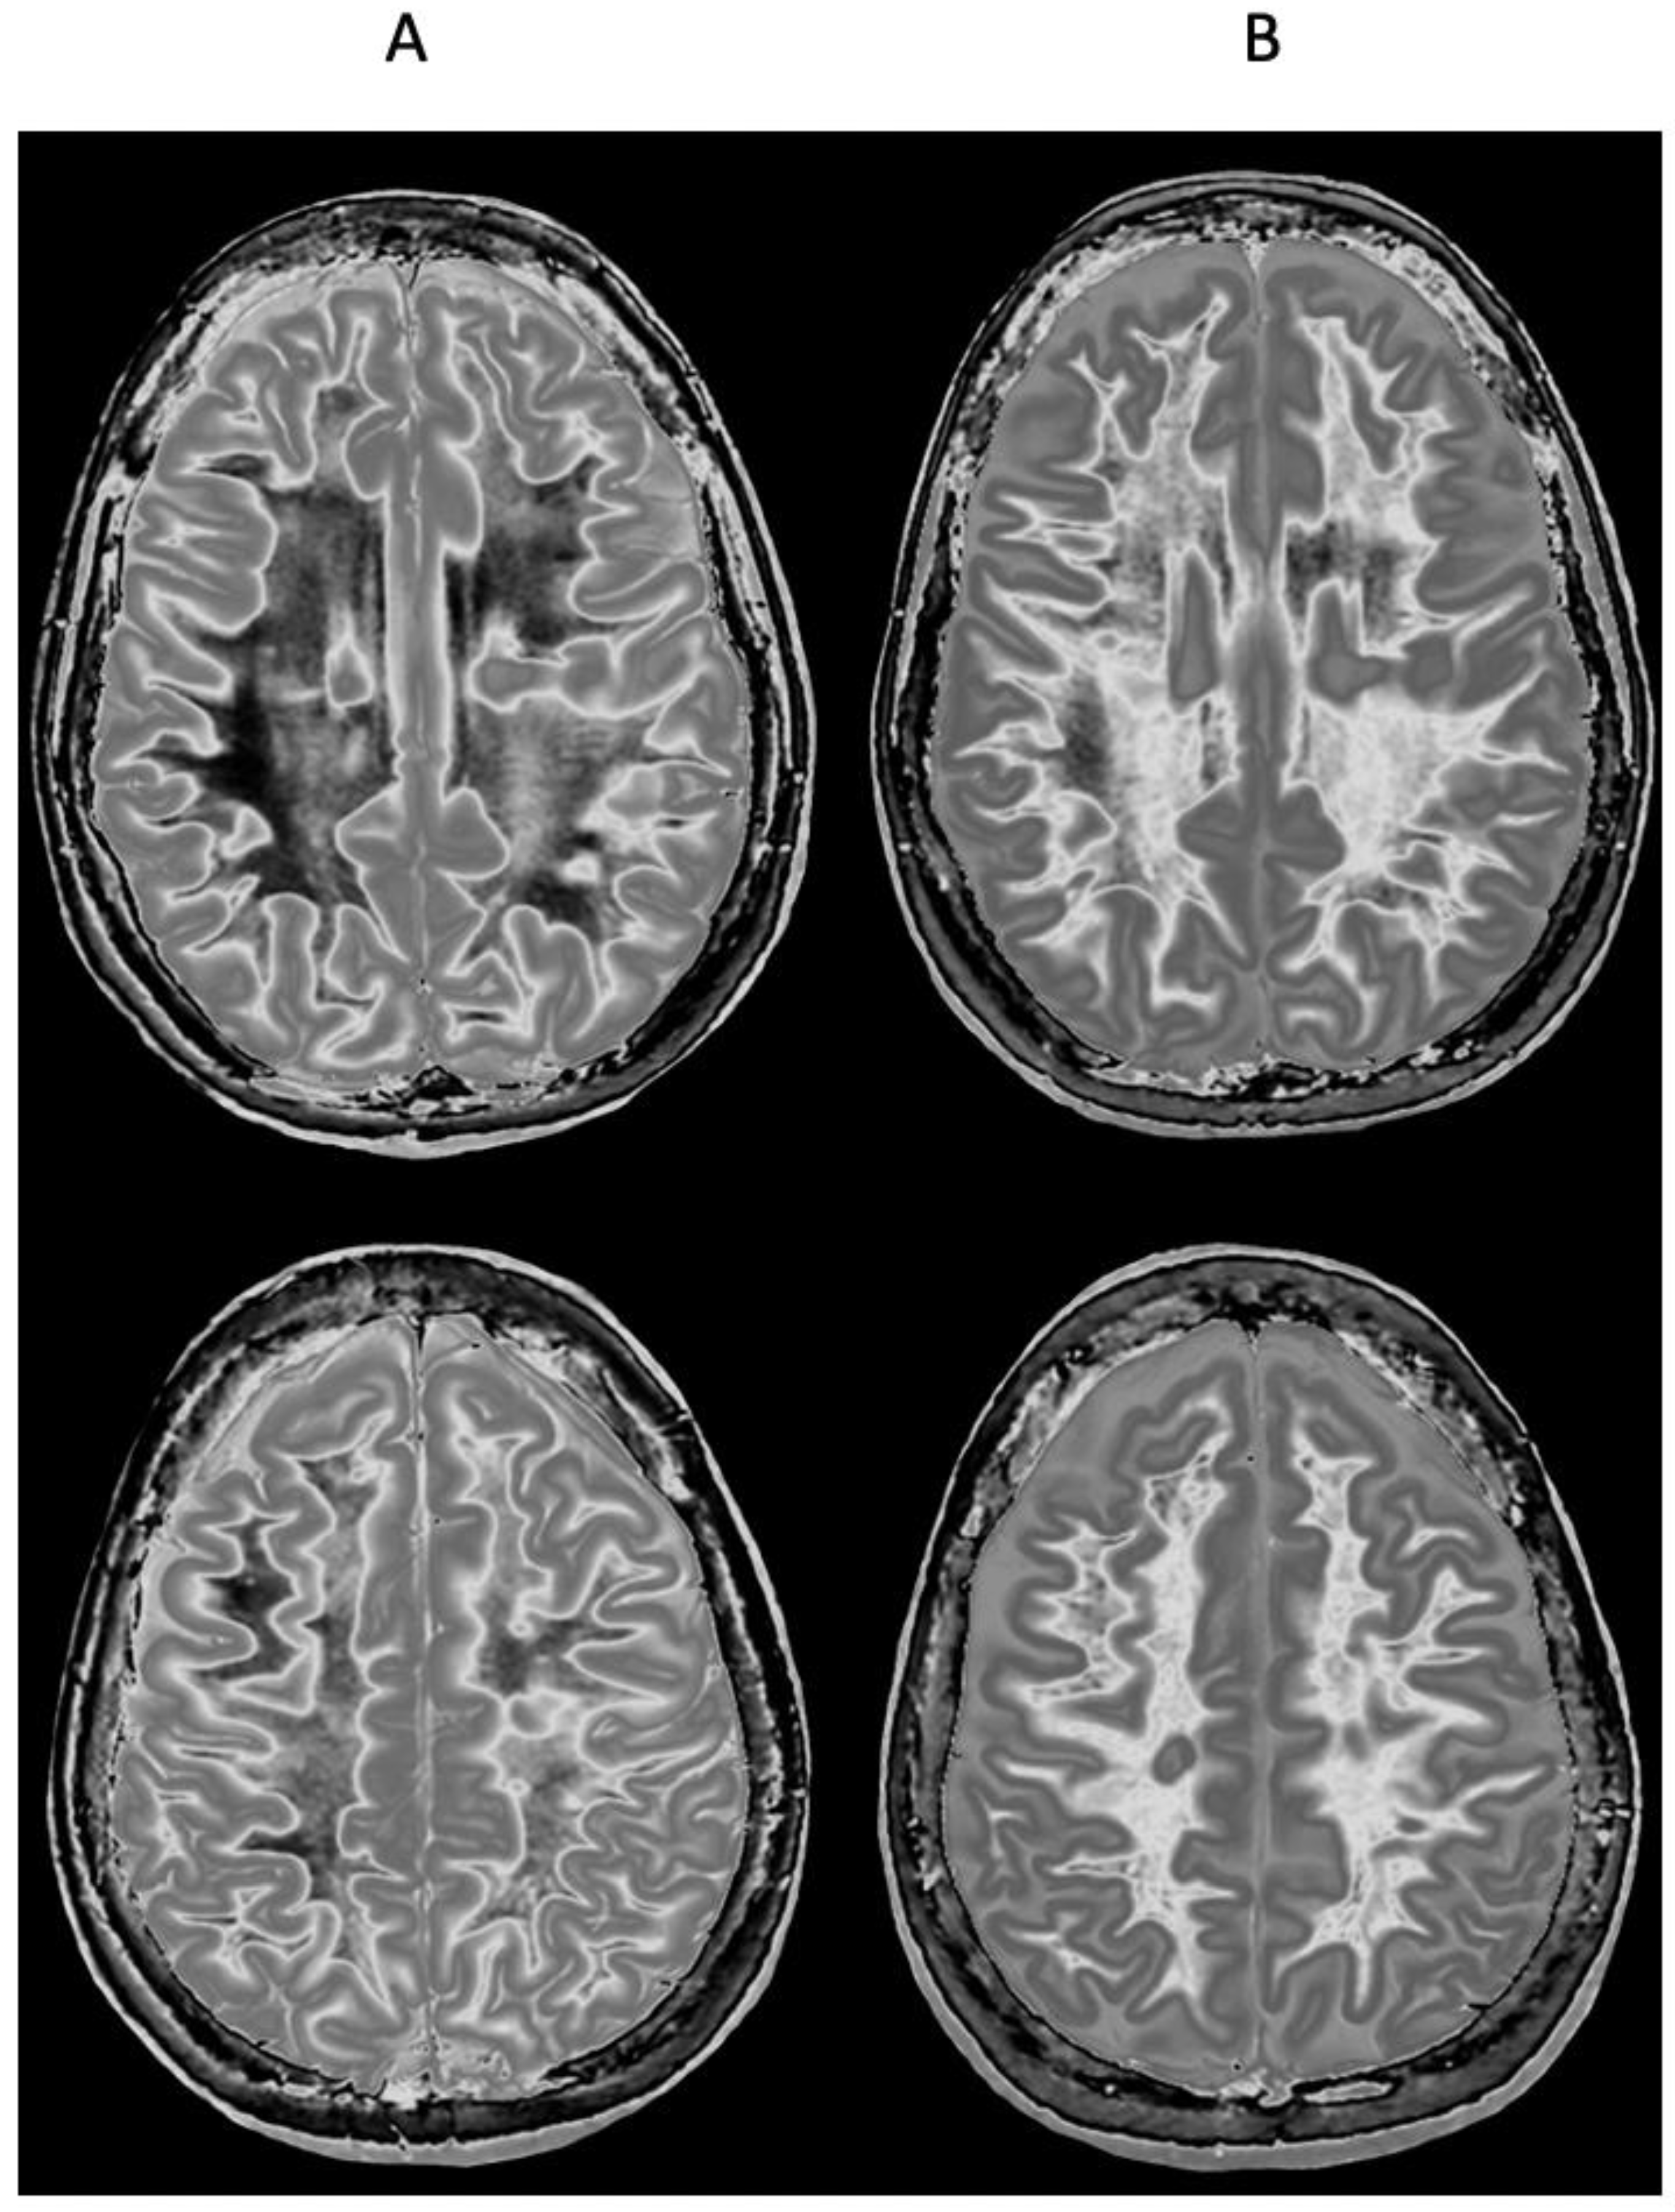

Figure 9 and Figure 10 show a 38-year-old patient with MS in remission (Figure 9A and Figure 10A, left columns) and during a relapse two years and five months later (Figure 9B and Figure 10B, right columns) imaged with the same narrow mD dSIR sequence. Figure 9 shows three positionally matched lower levels in the brain and Figure 10 shows two positionally matched higher levels in the brain. White matter shows a generally low signal during remission (whiteout sign grade 1–2) (Figure 9A and Figure 10A), and a high signal (whiteout sign grade 4–5) during the relapse (Figure 9B and Figure 10B). The multiple levels within the brain show the wide distribution of the high grade whiteout sign in the cerebellar and cerebral hemispheres, as well as in the brainstem. No evidence of a whiteout sign was seen on the corresponding T2-FLAIR images.

Figure 9.

Thirty-eight-year-old female patient with MS in remission (A, left column) and during a relapse (B, right column) two years and five months later. Matching narrow mD dSIR images at three lower levels in the brain. In remission (left column), there are bilateral symmetrical areas of low signal in the white matter of the cerebellar and cerebral hemispheres. The corresponding areas show increased signal during the relapse (right column) consistent with a grade 4–5 (out of 5) whiteout sign. No evidence of a whiteout sign was seen on the T2-FLAIR images.

Figure 10.

Thirty-eight-year-old female patient with MS in remission (A, left column) and during a relapse (B, right column) two years and five months later (same case as in Figure 9). Matching narrow mD dSIR images at two higher levels in the brain. In remission, white matter shows a low signal (left column). This is increased during the relapse in a bilateral symmetrical distribution consistent with a grade 4–5 (out of 5) whiteout sign (right column). No evidence of a whiteout sign was seen on the T2-FLAIR images.